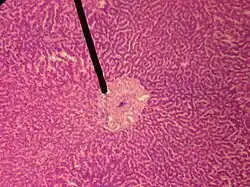

![]() human central vein | |

In microanatomy, the central veins of liver (or central venules)[1] are veins found at the center of hepatic lobules (one vein at each lobule center).

They receive the blood mixed in the liver sinusoids and return it to circulation via the hepatic veins.[2]

The circulation of venous blood is: portal vein (which is formed by the joining of the superior mesenteric vein with the splenic vein) drains into the sinusoids of the liver, these all drain into the central veins of liver which drain into the hepatic vein to be returned to IVC.